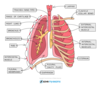

Gas Exchange in Humans (Picture)

The alveolus is the gas exchange surface in humans

Structure of the Breathing System